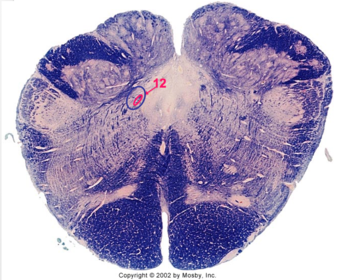

| Nucleus gracilis | |

| Nucleus cuneatus | |

| Fasciculus gracilis | |

| Fasciculus cuneatus | |

| Internal acruate fibers | |

| Lateral (external/accessory) cuneate nucleus | |

| Medullary pyramids | |

| Hypoglossal nucleus | |

| Hypoglossal nerve | |

| Dorsal motor nucleus of X | |

| Nucleus ambiguus | |

| Solitary tract | |

| Solitary nucleus | |

| ALS | |

| Medial lemniscus | |

| Medial longitudinal fasciculus | |

| Spinal tract of V | |

| Spinal nucleus of V | |

| Lateral (external, accessory) cuneate nucleus | |